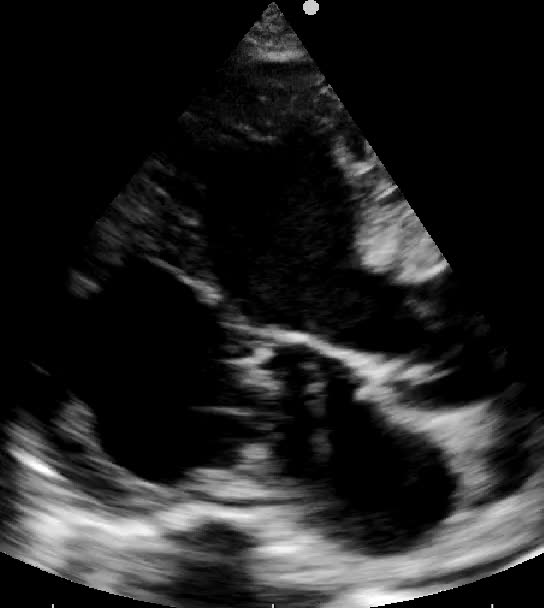

Titolo:

Trombosi della vena cava inferiore in embolia polmonare

Autore:

Chiara Bencini